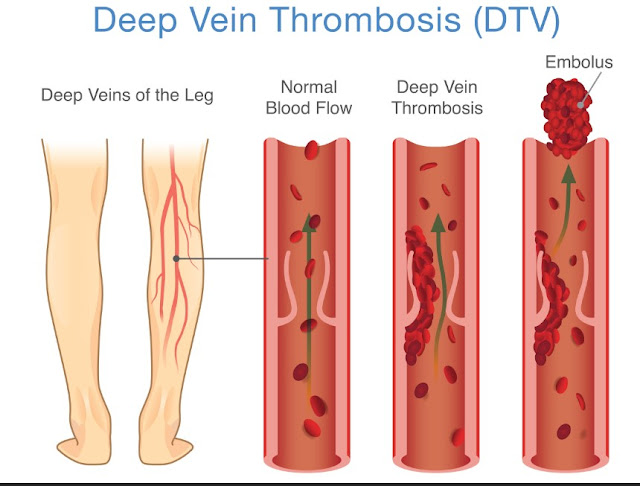

Deep vein thrombosis

One of the most serious explanations for sudden swelling in a single foot or calf is a deep vein thrombosis, often called a DVT. This is a blood clot that forms in a deep vein, usually in the lower leg. Because the clot blocks normal blood flow, fluid backs up and the leg becomes puffy. The area may feel tender, heavy, or warm, and the skin can look red or slightly blue. Some people notice the discomfort most when they stand or walk, or they feel a tight, cramping sensation in the calf.

A DVT needs medical attention right away because part of the clot can travel to the lungs and cause a life-threatening condition called a pulmonary embolism. Call emergency services if swelling comes with chest pain, sudden shortness of breath, coughing up blood, a racing heartbeat, or feeling faint. Even without those symptoms, if one leg is clearly larger than the other and you have pain or warmth, it is important to be seen promptly. A quick ultrasound can confirm the diagnosis, and treatment can protect you from serious complications.

DVTs are more likely after long travel or bed rest, recent surgery, a leg injury, or if you have certain medical conditions. Smoking, being overweight, taking hormone therapy, and a family history of clots can also raise risk. If you often sit for long periods, taking short walking breaks, flexing your ankles, and staying well hydrated can help keep blood moving.